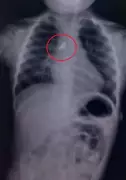

India's fight against tuberculosis is undergoing a technological revolution. Molecular diagnostics like GeneXpert and Truenat have replaced century-old microscopy, while AI-powered chest X-rays and tongue-swab tests promise to reach millions more.